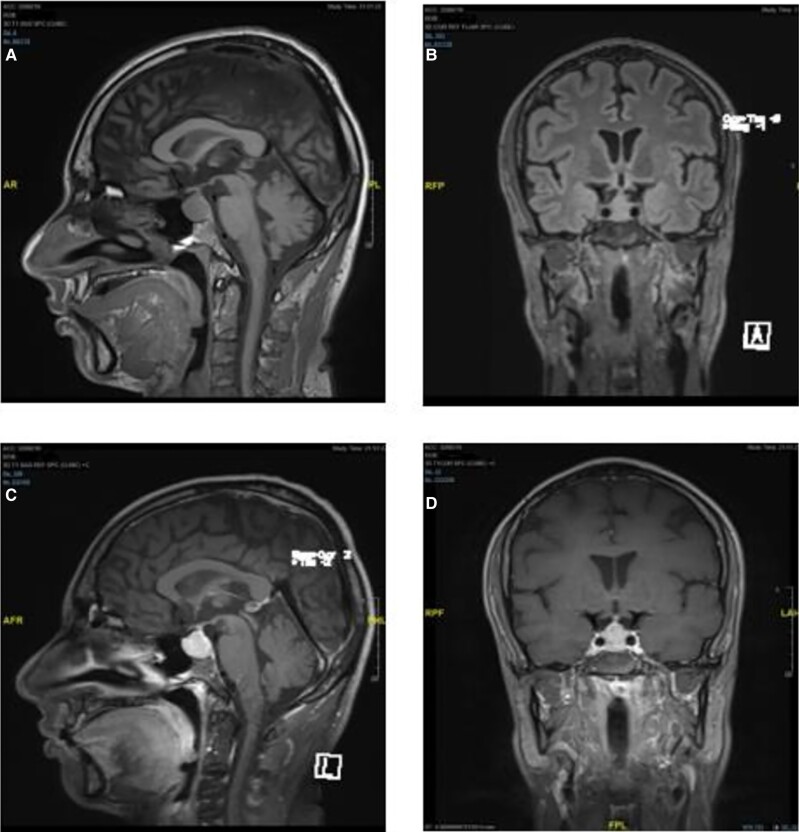

Thyrotroph hyperplasia is commonly present but remains largely undiagnosed in primary hypothyroidism. It is easily reversible with thyroid replacement therapy. If imaging is performed prior to biochemical evaluation, then patients may undergo pituitary surgery unnecessarily. We present the case of a 30-year-old man with thyrotroph hyperplasia caused by profound primary hypothyroidism leading to hypopituitarism that resolved after levothyroxine replacement therapy. We will discuss the current literature regarding pituitary hyperplasia in primary hypothyroidism in adults.

Abstract Image